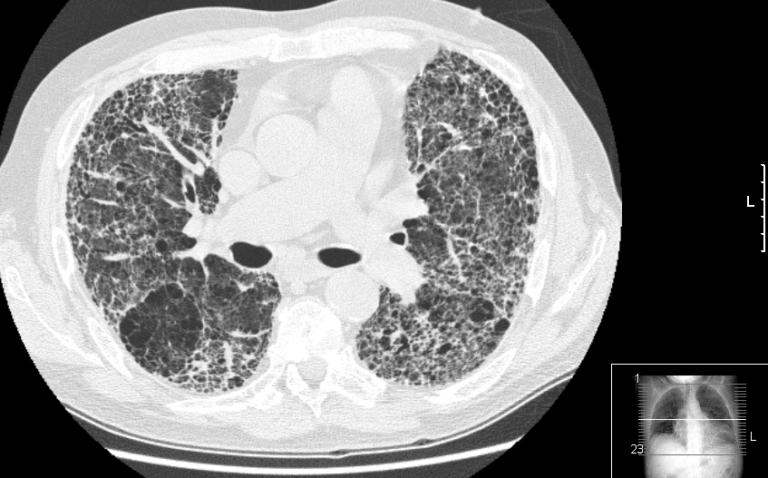

Proto je nesmírně důležité nasadit včas léčbu, která procesu jizvení brání,“ vysvětluje přednostka Pneumologické kliniky Fakultní Thomayerovy nemocnice a 1. LF UK prof. MUDr. Martina Koziar Vašáková, Ph.D. Jak dále uvádí, od roku 2022 do 2024 absolvovalo v rámci screeningu rakoviny plic vyšetření s pomocí nízkodávkového CT 14 989 rizikových osob.

U 3,5 % (464 osob) lékaři jako sekundární nález objevili fibrotické změny na plicích. Z těchto 464 osob bylo u 6,0 % (28) nakonec diagnostikováno intersticiální plicní onemocnění.

Fibrózy se často pojí s jinými nemocemi, jako je například revmatoidní artritida nebo systémová sklerodermie. Nejzávažnější formou plicních fibróz je tzv. idiopatická plicní fibróza, která bez léčby zabíjí do 2–5 let.

Tu má v ČR dle odhadů odborníků přes 1 300 osob. Antifibrotickou léčbu, která postup nemoci zpomaluje, však užívá jen asi 800 z nich. „Nemoc se zpočátku projevuje únavou a postupně sílící dušností při námaze.